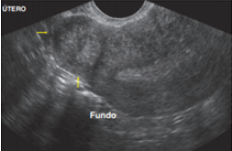

19

Q

qual o diagnóstico

A

Mioma